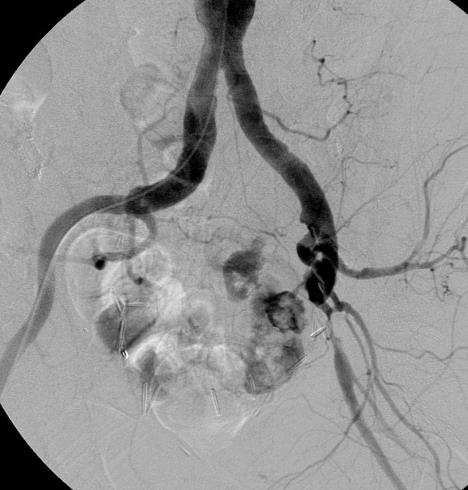

髂动脉损伤:肿瘤

|

出血,造影剂外溢 |

假性动脉瘤 |

造影剂外溢 |

覆膜支撑架 |

Knape et al. J Endovasc Ther 2004